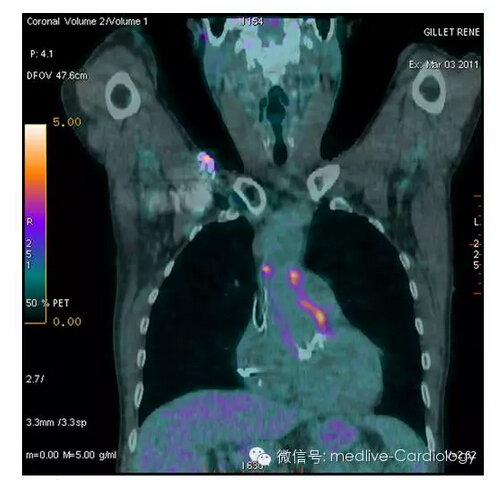

图4 18氟脱氧葡萄糖正电子成像,患者在Bentall手术后2个月出血葡萄球菌败血症,无超声心动图异常